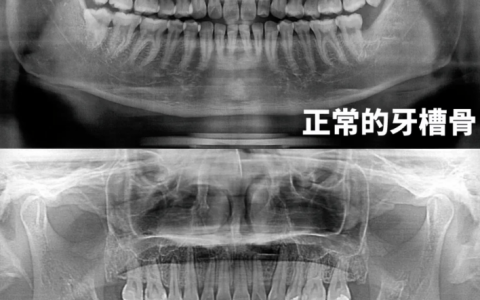

良心医生建议能做假牙就不要做种植牙是有前提的,能做假牙就不要种植牙的绝对性的观点是不正确的,可根据经济条件、牙槽骨厚薄等,选择假牙或种植牙。种植牙费用较高,若经济条件不允许,可考虑假牙。另外,若牙槽骨较薄,无法支撑牙桩,种植牙后使用寿命较短时,建议做假牙。

假牙包括固定假牙、活动假牙,通过固定假牙修复牙齿时,通常会打磨固定邻牙,会对邻牙造成损伤。若固定邻牙受损,通常需拆除假牙。口腔基础条件较差的老年人可使用活动假牙修复,但该牙齿对口腔卫生条件要求较高,需早晚、饭后摘除清洁。该牙齿常使患者有异物感,舒适度较差,长期使用可能导致牙槽骨吸收。种植牙时通常不会对邻牙造成损伤,与假牙相比种植牙的舒适度更高,可最大程度的恢复咀嚼功能,使用寿命长。若能做假牙也能做种植牙,一般建议种植牙。